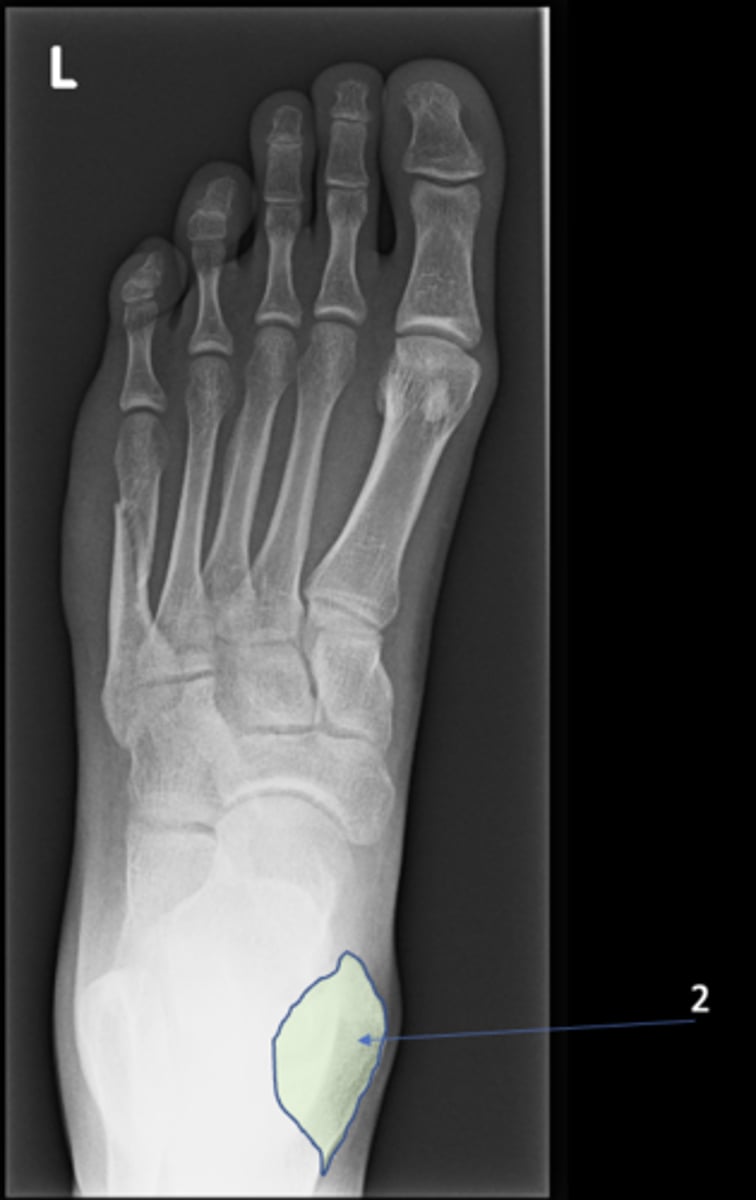

New cards

Left inferior pubic ramus

ID 15

<p>ID 15</p>

15

S1 tubercle

ID 16

<p>ID 16</p>

16